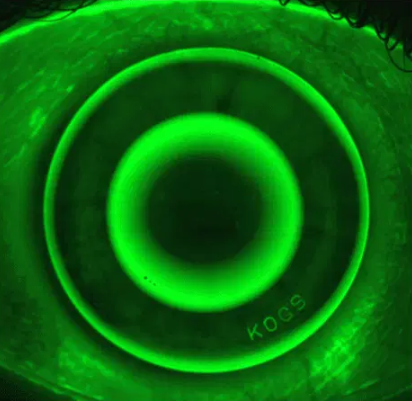

City Eye Care is proud to be one of the few private practitioners in Indore to offer specialised Orthokeratology (Ortho-K) services. This revolutionary, non-surgical treatment involves wearing specially designed gas-permeable contact lenses overnight to reshape the cornea gently. Whether you are looking for myopia control in children to slow down the progression of nearsightedness or seeking cosmetic correction to enjoy clear vision during the day without glasses or surgery, our full-fledged Ortho-K program provides a safe, reversible, and effective solution tailored to your clinical needs.

Orthokeratology utilizes custom-engineered lenses to subtly reshape the cornea during sleep. By precision-tuning how light focuses onto the retina, this non-surgical therapy effectively corrects myopia, hyperopia, and astigmatism, allowing patients to enjoy clear, natural vision throughout the day without the need for glasses or daytime contacts

Acting as the eye’s natural lens, the cornea must be perfectly shaped to focus light clearly. If its curve is slightly off, your vision becomes blurred. Ortho-K lenses provide a non-invasive solution by gently calibrating the cornea’s shape overnight. The result is a temporary correction that restores visual clarity throughout your waking hours, offering a glasses-free lifestyle without the need for surgery.